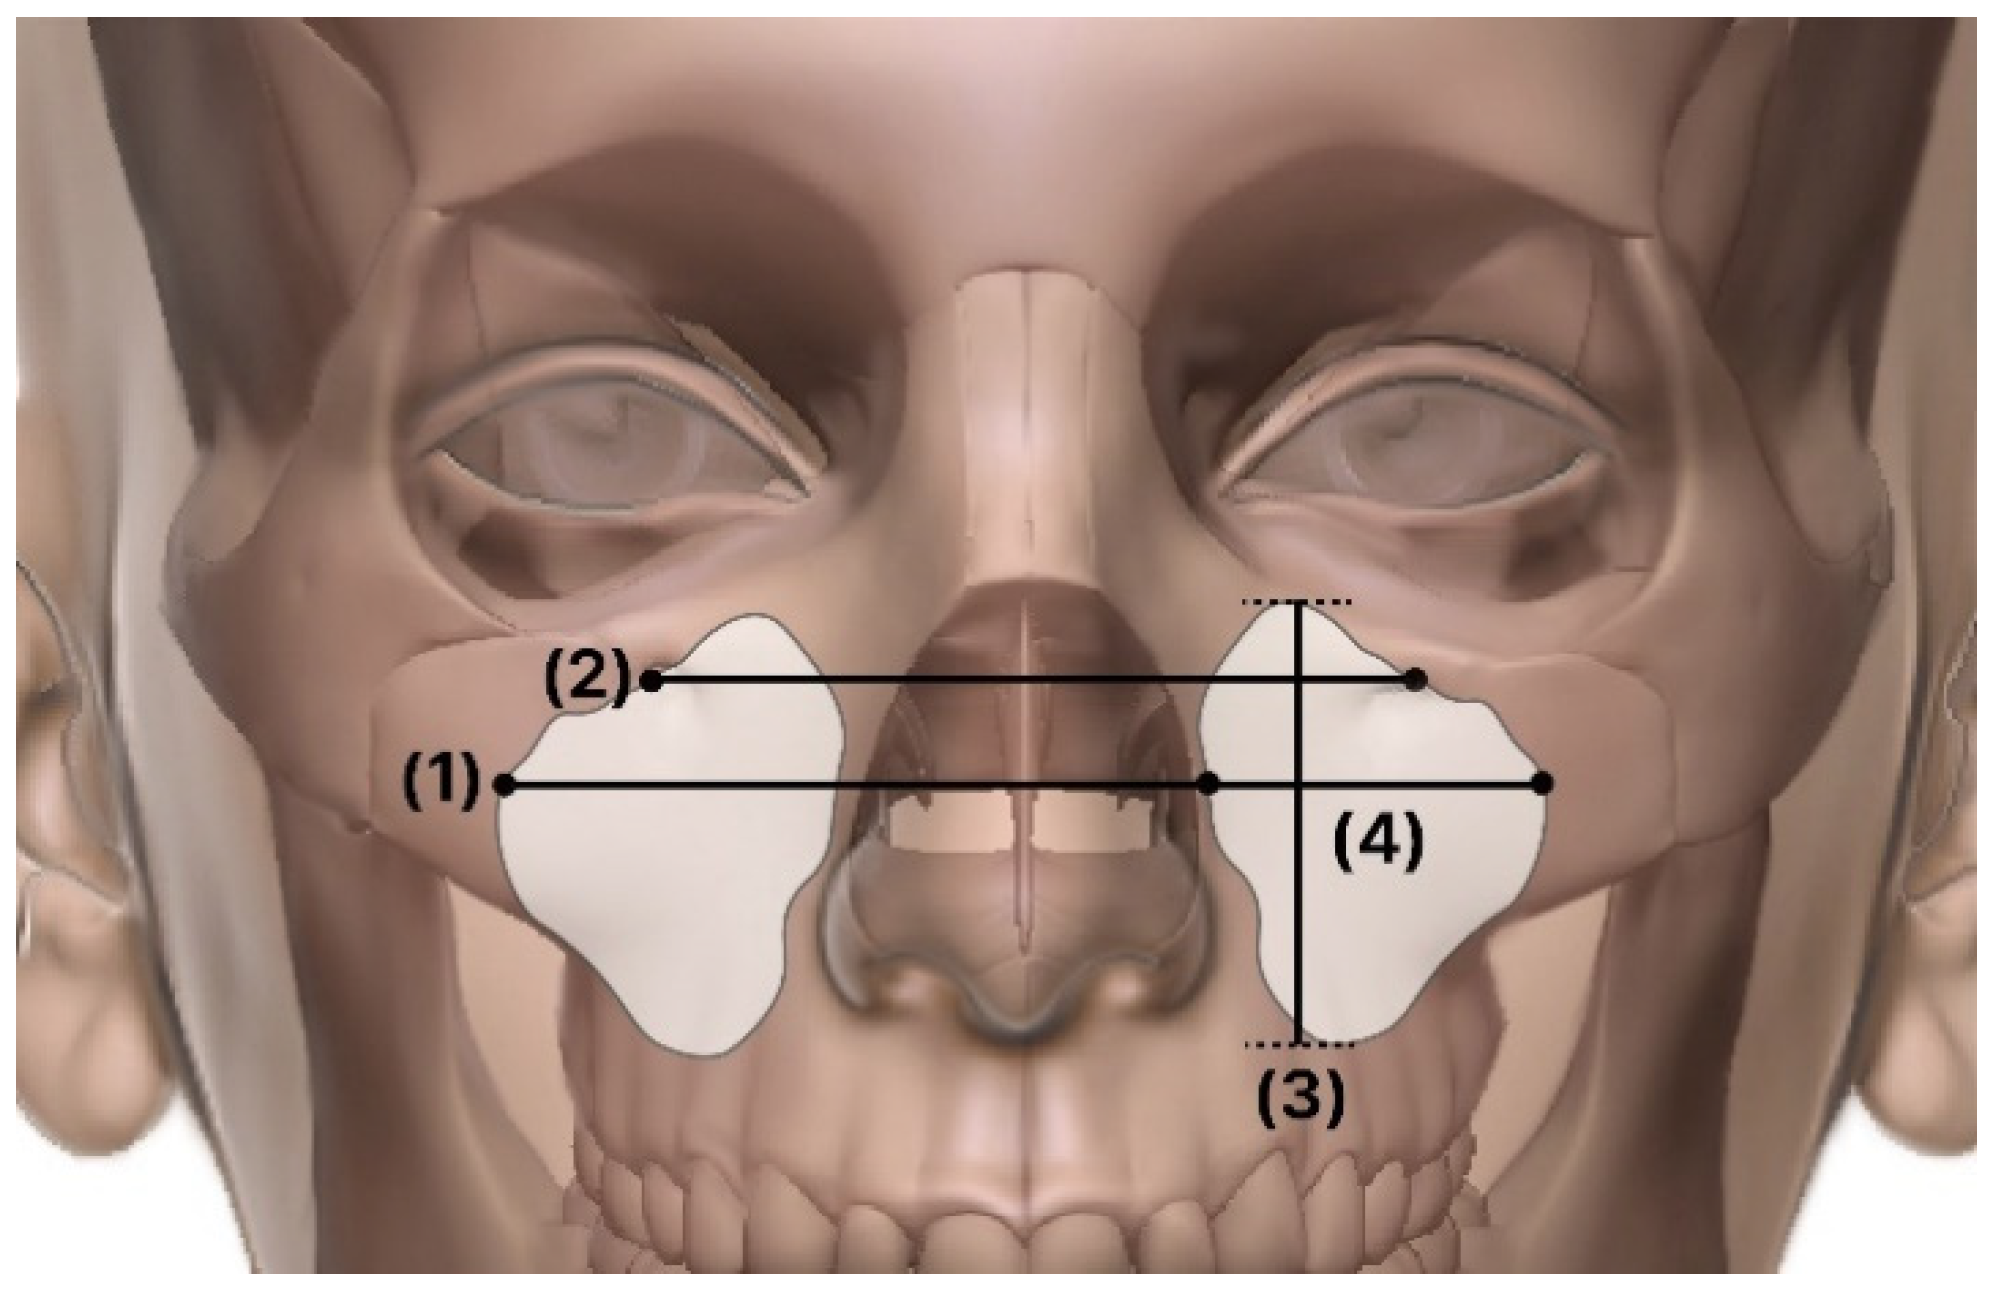

- IOF: distance between the infraorbital foramen from one side to the other.

- Right–left sinus distance: distance between the left and right maxillary sinuses.

- Width: corona-view width.

- Length: sagittal-view width

- Height: maxillary sinus height.

- Volume: maxillary sinus volume.